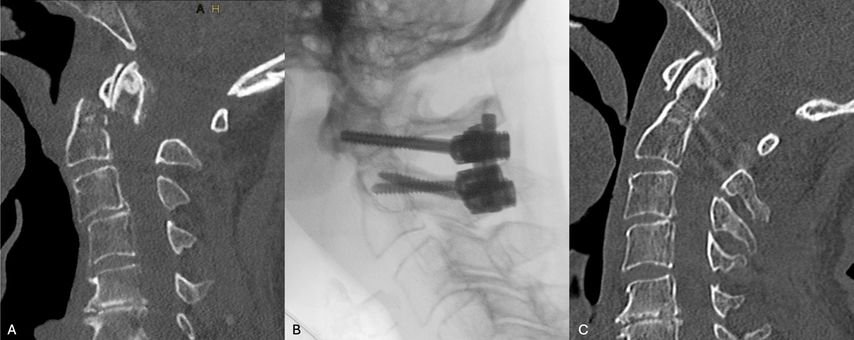

Abb. 2: Dislozierte Densfraktur mit inkomplettem Querschnittssyndrom (A); intraoperatives Bild der C1/2-Stabilisierung (B); postoperative CT-Kontrolle(C)

Die posteriore C1/C2-Instrumentation nach Goel/Harms wird international mittlerweile zur Stabilisierung dislozierter geriatrischer Densfrakturen bevorzugt, da sie biomechanisch eine höhere Stabilität gegenüber der anterioren Densverschraubung aufweist. Dies ist v.a. bei transdentalen Luxationsfrakturen sowie Ankylose der subaxialen HWS vorteilhaft. Diese posteriore Fixierung bietet eine zuverlässige Möglichkeit zur Stabilisierung von Densfrakturen und sehr hohe knöcherne Heilungsraten, geht jedoch mit einer zumindest 50%igen Reduktion der Seitrotation einher. Weitere Nachteile sind die intraoperativ erforderliche Bauchlagerung, der höhere Blutverlust (Blutung aus dem epiduralen bzw. periradikulären Venenplexus bei der Platzierung der C1-Schrauben) und die längere OP-Dauer. Zudem können atypische Verläufe der A. vertebralis die Platzierung der C2- und C1-Schrauben sehr risikoreich oder gar unmöglich machen. In diesen Fällen muss eine Modifikation der Stabilisierungstechnik vorgenommen werden (z.B. Platzierung von kurzen Isthmus- oder Laminaschrauben statt C2-Pedikelschrauben) oder ein anteriores Verfahren gewählt werden.

Die anteriore Densverschraubung ermöglicht den Erhalt der atlantoaxialen Bewegung und hat zusätzlich Vorteile wie eine intraoperative Lagerung in Rückenlage, kürzere Operationszeit und geringeren Blutverlust. Einige Frakturmorphologien (Typ IIc nach Grauer, Trümmerzonen) sowie Körperhabitus (kurzer Hals, Fassthorax sowie zervikale oder thorakale Kyphose) können die Anwendung der anterioren Fixierung jedoch einschränken oder unmöglich machen. Bei älteren Patienten wird die Effektivität der anterioren Fixierung von einer Reihe von Autoren infrage gestellt, da sie mit einer relativ hohen Rate an Komplikationen wie Pseudarthrose, mechanischen Komplikationen und Dysphagie verbunden ist.22 Insbesondere letztere wird bei hochbetagten Patienten ungleich häufiger beobachtet und kann Aspirationspneumonien und die Notwendigkeit einer Ernährung über eine transnasale Magensonde bzw. PEG-Sonde zur Folge haben. Die anteriore Densverschraubung erlaubt es zwar, eine C1/C2-Fixation zu vermeiden, was für jüngere Patienten ohne erhöhtes Sterberisiko sowie mit guter Knochenqualität relevant ist, jedoch zeigen mehrere Studien, dass dieses Stabilisierungsverfahren in einem geriatrischen Patientenkollektiv mit mehr Komplikationen und Revisionseingriffen verbunden ist. Studien in einer geriatrischen Population ergaben, dass Patienten, die sich einer Densverschraubung unterzogen, im Vergleich zur posterioren Stabilisierung ein höheres Risiko für Pseudarthrosen (25,5% gegenüber 3,5%) und Revisionseingriffe (23,4% gegenüber 10,5%) hatten.23